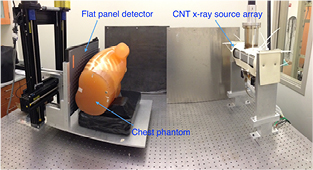

A bench-top system was set up using a linear x-ray source array containing 75 focal spots and a flat panel detector, as shown in figure 1. The linear source was characterized. The x-ray output and beam quality were measured. Focal spot sizes of multiple spots were measured using pinhole. Projection images of a cross wire phantom were acquired and reconstructed to measure the system modulation transfer function (MTF) and the artifact spread function (ASF) as quantitative measurements of the system in-plane resolution and in-depth resolution, respectively.

Figure 1. Bench-top stationary chest tomosynthesis system. The linear CNT x-ray source array consists of 75 x-ray generating focal spots. The detector and phantom, mounted on the same stage, can be translated to simulate different imaging geometries.

2.2. System description

The bench-top chest tomosynthesis system, as shown in figure 1, consists of the CNT linear x-ray source array, a CsI based flat panel detector (Model DRX-1C) manufactured by Carestream Health Inc. (Rochester, NY) mounted on a translation stage, a phantom stage, and an electronic control unit. The detector, which was originally designed for radiographic imaging purpose, has a field of view of 35 × 43 cm and a 139 μm pixel size. The integration time can be adjusted from 260 to 1100 ms. The detector requires a frame by frame external trigger to acquire a sequence of images. Since the x-ray source array used in this study has a relatively short length, the detector and the phantom are mounted on a translation stage to achieve a wider range of imaging geometries. A LabVIEW program was made to automate the x-ray tube operation and image acquisition. As illustrated in the timing diagram in figure 2, the computer generates a sequence of trigger signals to trigger the detector read-out, followed by the detector ready-to-exposure signal which is synced to the x-ray source switching system. The x-ray source switching system is programed to switch and fire each x-ray source based on the sequence set by the operator. The x-ray sources can be fired in any sequence, either one-by-one from one end to the other, or in a pre-defined pattern.

2.6. Anthropomorphic phantom imaging

Projection images of an anthropomorphic phantom (Kyoto Kagaku Co. Ltd, Kyoto, Japan) were acquired and reconstructed into tomosynthesis slices. The phantom was positioned as shown in figure 1. The scanning direction was along the axis of the spine (superior–inferior direction), as commonly used in previous studies, to reduce the limited angular artifacts of the ribs (Dobbins and McAdams 2009, Vikgren et al 2008, Tingberg 2010). The projection images were acquired at 80 kVp and 0.6 mAs exposure per projection. The images were reconstructed using the RTT software with 4 mm slice spacing for image quality assessment.